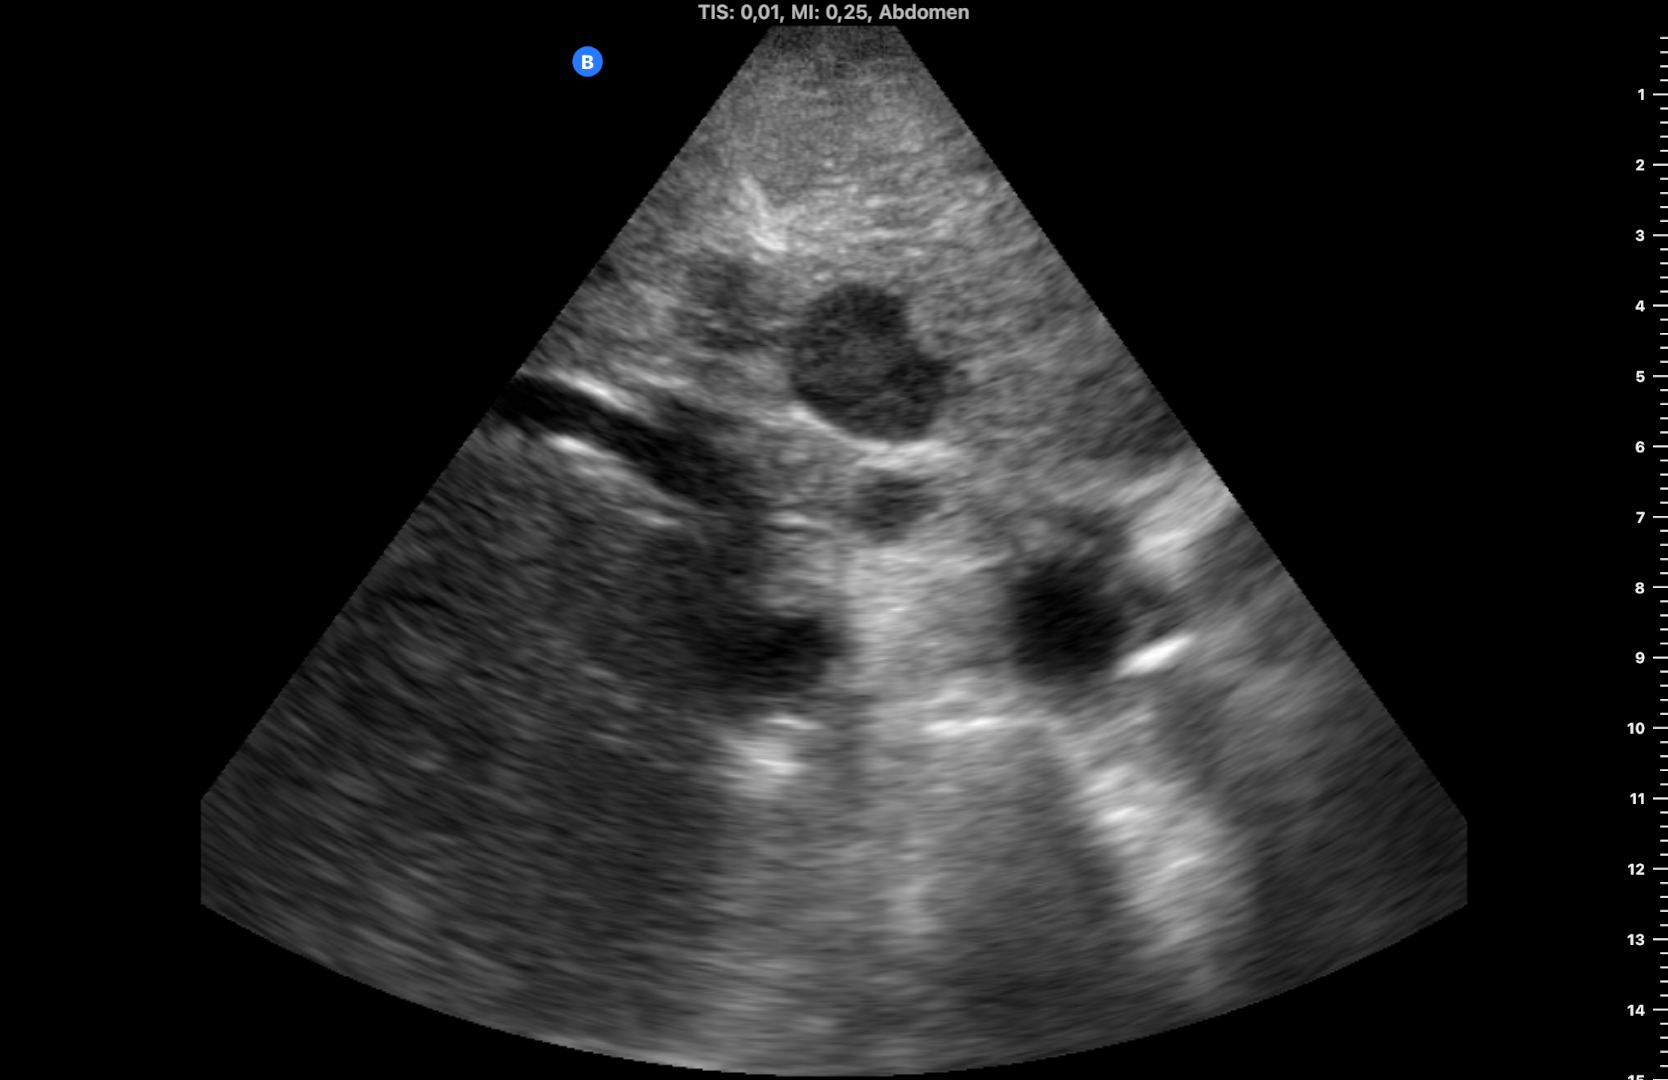

Seis meses después, al revisar la historia su médico advierte que el paciente olvidó su cita y vuelve a derivarlo tras realizar otra ecografía clínica, observando las mismas lesiones sin cambios (figura 4), lo que sugería benignidad. Finalmente se realiza TC: «lesión hipodensa de apariencia sólida en lóbulo caudado de 14 mm y lesión subcapsular de 9 mm en segmento VIII» y RM: «múltiples lesiones hepáticas benignas, la mayoría corresponden a angiomas hepáticos (los de mayor tamaño se localizan en los segmentos 1 y 3), otras se corresponden a pequeños quistes biliares subcentimétricos».

Aunque un aparente síndrome constitucional (en esta ocasión debido a su situación social) y LOES hipoecogénicas hepáticas inicialmente pueden sugerir malignidad, debe mantenerse una actitud prudente hasta la confirmación diagnóstica. Los angiomas suelen verse como lesiones hiperecogénicas bien delimitadas pero pueden tener presentaciones atípicas.